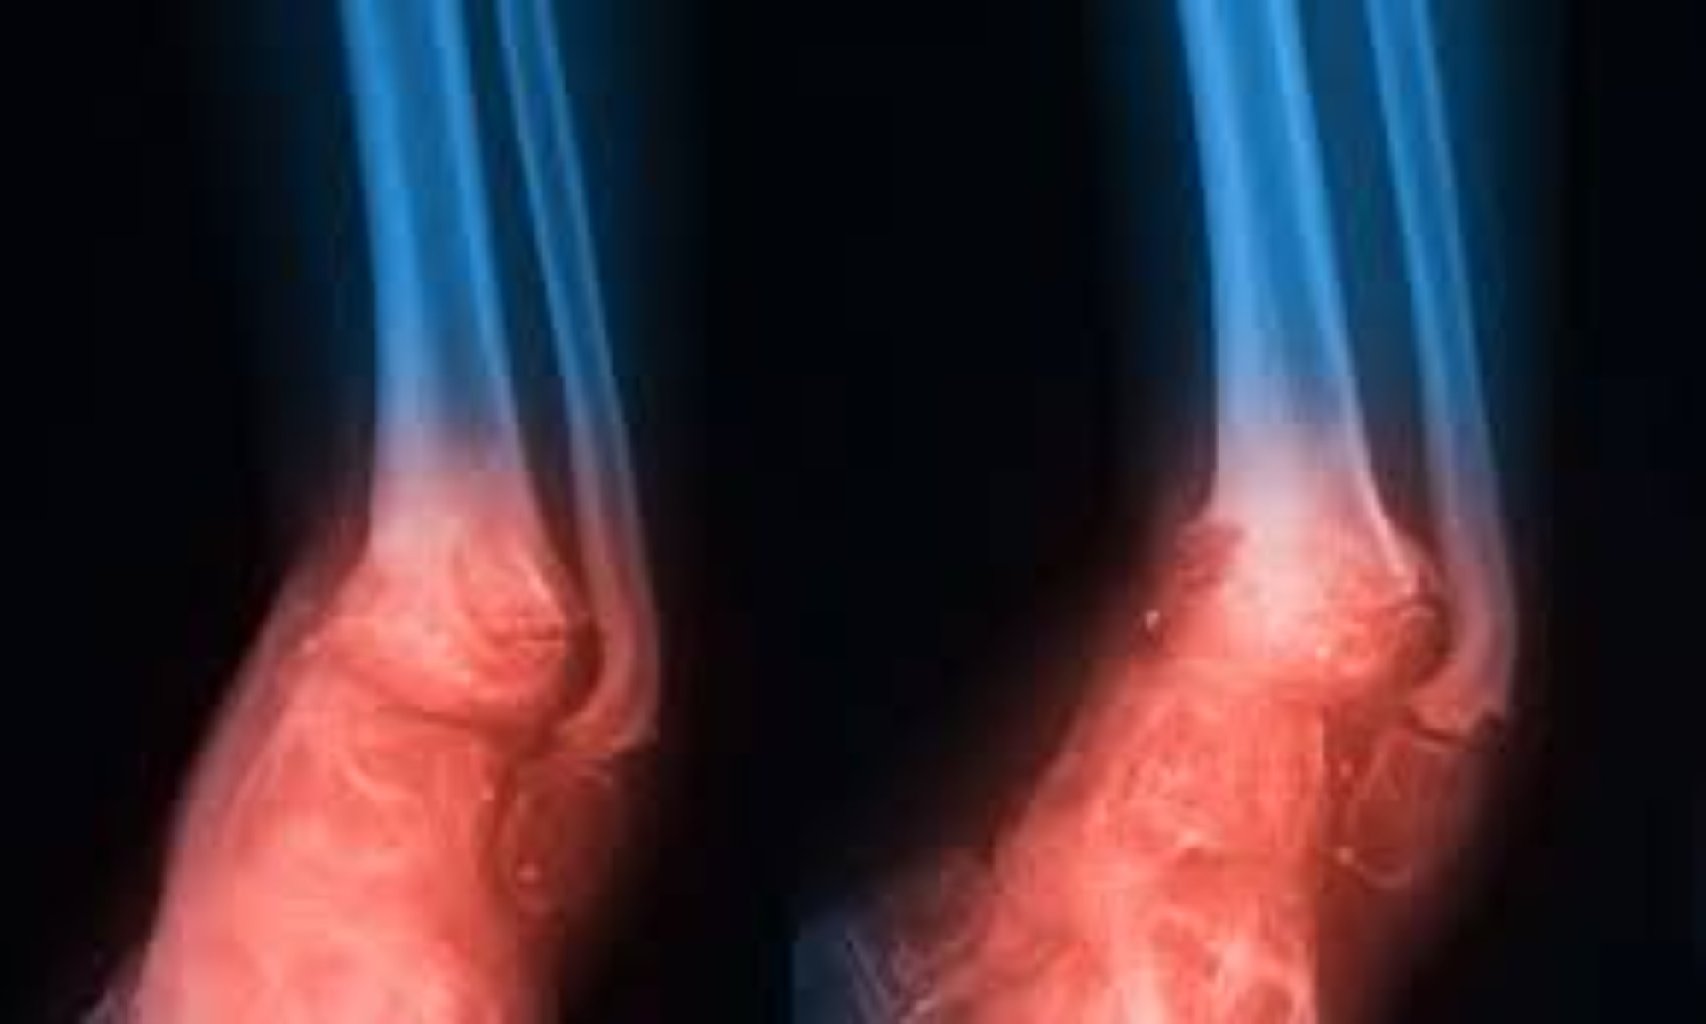

Diz Artroplastikası (Diz Protezi): Diz protezi əməliyyatı, diz oynağının zədələnmiş yüzeylərinin ...

Diz Protezi Əməliyyatı (Total Diz Artroplastisi): Diz protezi əməliyyatı, diz ekleminin aşınma və ...

Diz Artroskopik Cərrahiyyə: Diz artroskopiyası, menisk yırtıqları, çarpaz bağların zədələnməsi və qı ...